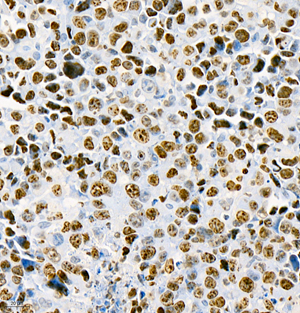

Images

| IHC analysis of ki67 (GB111141). Sample: Rat colon (Paraffin), 4% PFA (G1101) 12-24h. Antigen retrieval: Citrate buffer (pH 6.0) (G1201), pressure cooker 2min. Blocking buffer: 3% BSA in PBS (GC305010), RT, 30min. Primary antibody: 1: 750, 4°C overnight. Secondary antibody: HRP Goat Anti-Rabbit lgG (GB23303), 1: 200 RT 1h. |